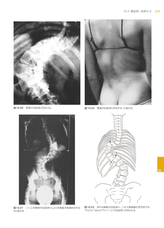

また、豊富な写真と図表でシュロス法を実践し、応用できるように解説。最新のエビデンスに基づく、側弯症の診断所見や根拠などの基礎知識から運動の方針と提案まで、幅広い知識と技術が習得可能です。成功例の治療経過やシュロス法の歴史的な成り立ちも紹介し、歴史と現在、原理と最新治療から包括的にシュロス法をお伝えします。